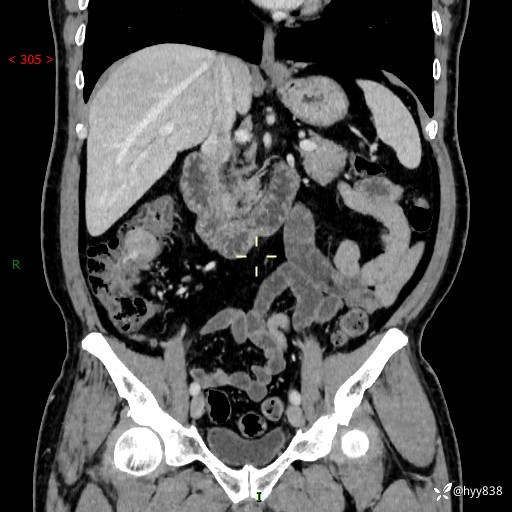

腹部CT增强扫描(外院CT平扫)

两期CT值:75hu 82hu